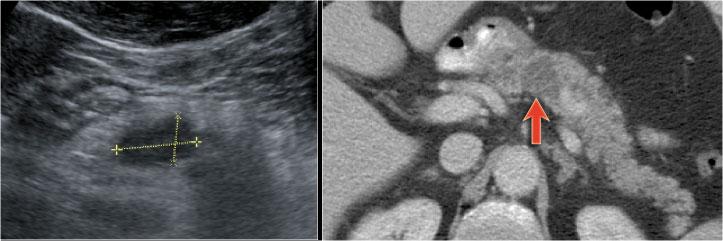

Hình ảnh CT của một IPMN với ống tụy giãn (mũi tên xanh).

Lưu ý nốt đặc có ngấm thuốc tại đầu tụy (mũi tên đỏ).

Tiếp tục xem hình ảnh siêu âm.

Hình ảnh siêu âm cho thấy thành phần ống nhánh kích thước lớn nằm trong đầu tụy.

Ở một nam giới 73 tuổi, phát hiện tổn thương giảm âm tại thân tụy, có hình ảnh tương tự tổn thương dạng nang.

CT cũng xác định được tổn thương nhưng không cung cấp thêm nhiều thông tin hữu ích.

Tiếp tục xem hình ảnh MRI.

Chuỗi xung T2W xóa mỡ nặng thể hiện rõ tổn thương đa nang với đường thông thương vào ống tụy.

Trường hợp này được chẩn đoán là IPMN thể ống nhánh.